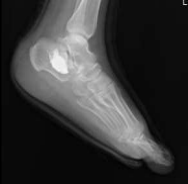

Postoperative Care and Optimizing Recovery and Monitoring Outcomes

Following the minimally invasive procedure, the patient's care focused on optimizing recovery and preventing potential complications. Thromboembolic prophylaxis with anticoagulants was resumed 12 hours postoperatively, Patient did not require much pain control and he was discharged home on the first postoperative day. Strict non-weight bearing on the left lower limb was enforced for the initial two weeks to allow for undisturbed fracture healing and soft tissue recovery. Regular follow-up appointments were scheduled within the orthopedic foot and ankle clinic to monitor progress and address any emerging concerns. Thromboembolic prophylaxis with Enoxaparin (40 mg once daily subcutaneously) was continued for two weeks following discharge. The dressing clinic visit within the first week confirmed no signs of infection or complications. Suture removal was performed at the two-week mark, revealing a well-healed wound with no soft tissue issues. After the initial non-weight bearing period, the patient progressed to partial weight bearing for gradual return to mobility. Follow-up radiographs (Figures 15, 16, and 17) were obtained to assess fracture alignment and stability. Additionally, a CT scan was performed within three weeks postoperatively (Figures 18, 19, 20, and 21) for in-depth evaluation of the internal components and fracture healing process. The crucial angle of Gissane on the follow-up CT scan measured approximately 145 degrees (Figure 22), indicating near-anatomical restoration of the posterior facet and a significant improvement from the initial measurements. Overall, the patient's postoperative course was uneventful, with no reported complications or concerns. Continued follow-up appointments and imaging at scheduled intervals will be crucial to monitor long-term fracture healing, maintain optimal outcomes, and address any potential issues that may arise.